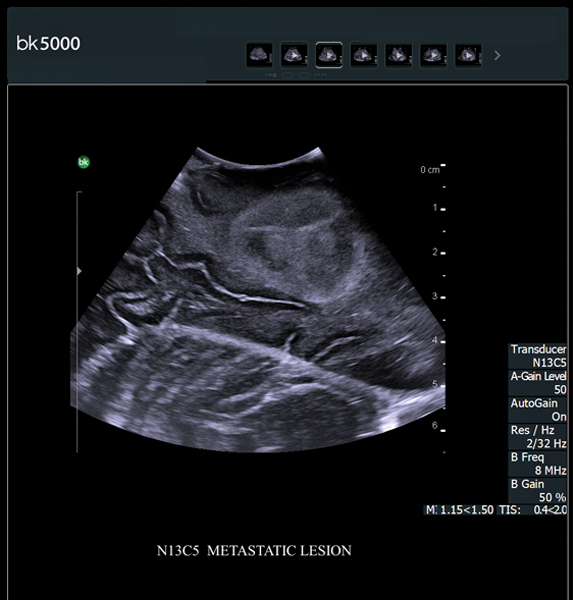

You know what you need, and you need it fast. That’s why the bk5000 is designed to deliver the high resolution images you count on quickly and efficiently. Whether you’re identifying margins of a lesion or making a general assessment of an area of interest, the bk5000 has the power and performance to meet your needs on your terms.